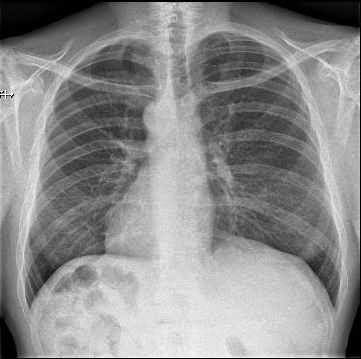

La placa de tórax PA y lateral es la siguiente.

Una masa mediastínica

Una masa bronquial que desplaza el mediastino hacia la derecha

Una debilidad diafragmática izquierda

Ninguna de las anteriores